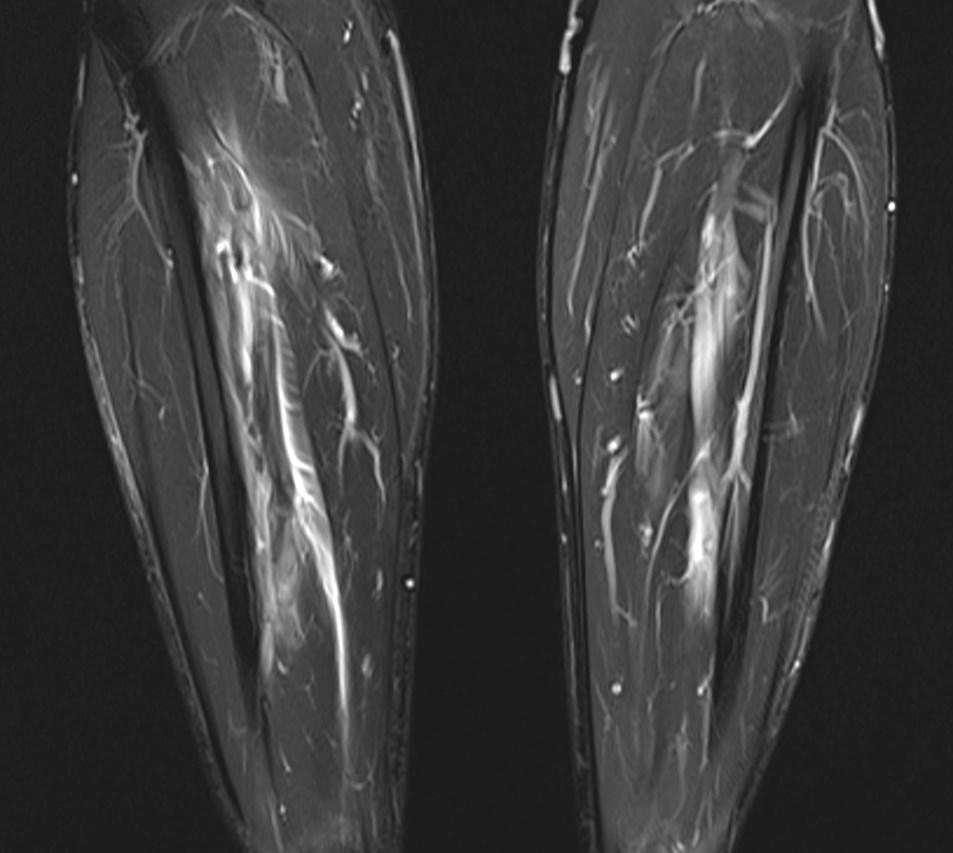

*29-year-old male present with pain in the right lower extremity for 3 days.

What is the most likely diagnosis?

Answer: Crural deep vein thrombosis

MR images showed perivascular edema, perifascial edema and the deep crural venous filling defects.